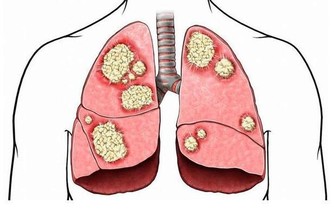

將白菜葉放在開水中泡軟後敷在患處, 可以治療燒傷、刀傷、血腫…… 據美國紐約一家專門從事癌症研究的權威機構透露, 中國和日本婦女乳腺癌的發病率比西方低得多, 這是為什麼呢?科學家在比較了世界各國的三餐食譜後得出結論:是由於中國和日本婦女多吃大白菜的緣故。

調查資料表明, 每10萬名婦女中, 每年乳腺癌的發病率為:中國9人, 日本21人, 北歐84人, 美國91人。

大白菜何來如此神功?實驗證明,

大白菜所含有的許多物質具有防癌抗癌的作用, 因此在美國國立癌症研究所發表的防癌食品排行榜中將白菜排在僅次於大蒜的後面,名列第二。